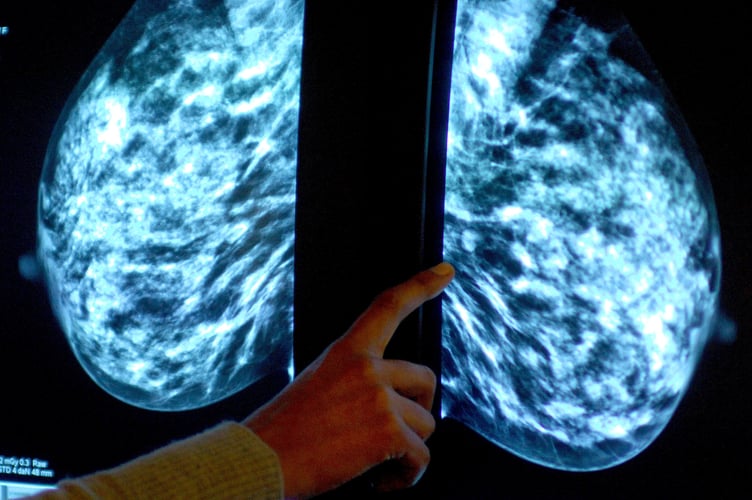

Anyone registered with a GP as female will be invited for NHS breast screening every three years between the ages of 50 and 71.

NHS England figures show 23,810 of the 35,080 people invited for a screening in the former NHS Kernow CCG had a test in the year to March this year.

It meant uptake of the screening stood at 68% – up from 67% the year before, but below pre-pandemic levels of 74% in 2019-20.

The figures show breast screening uptake across England increased to 65% last year from 63% in 2021-22. However, it remained well below pre-pandemic levels when 70% was recorded.